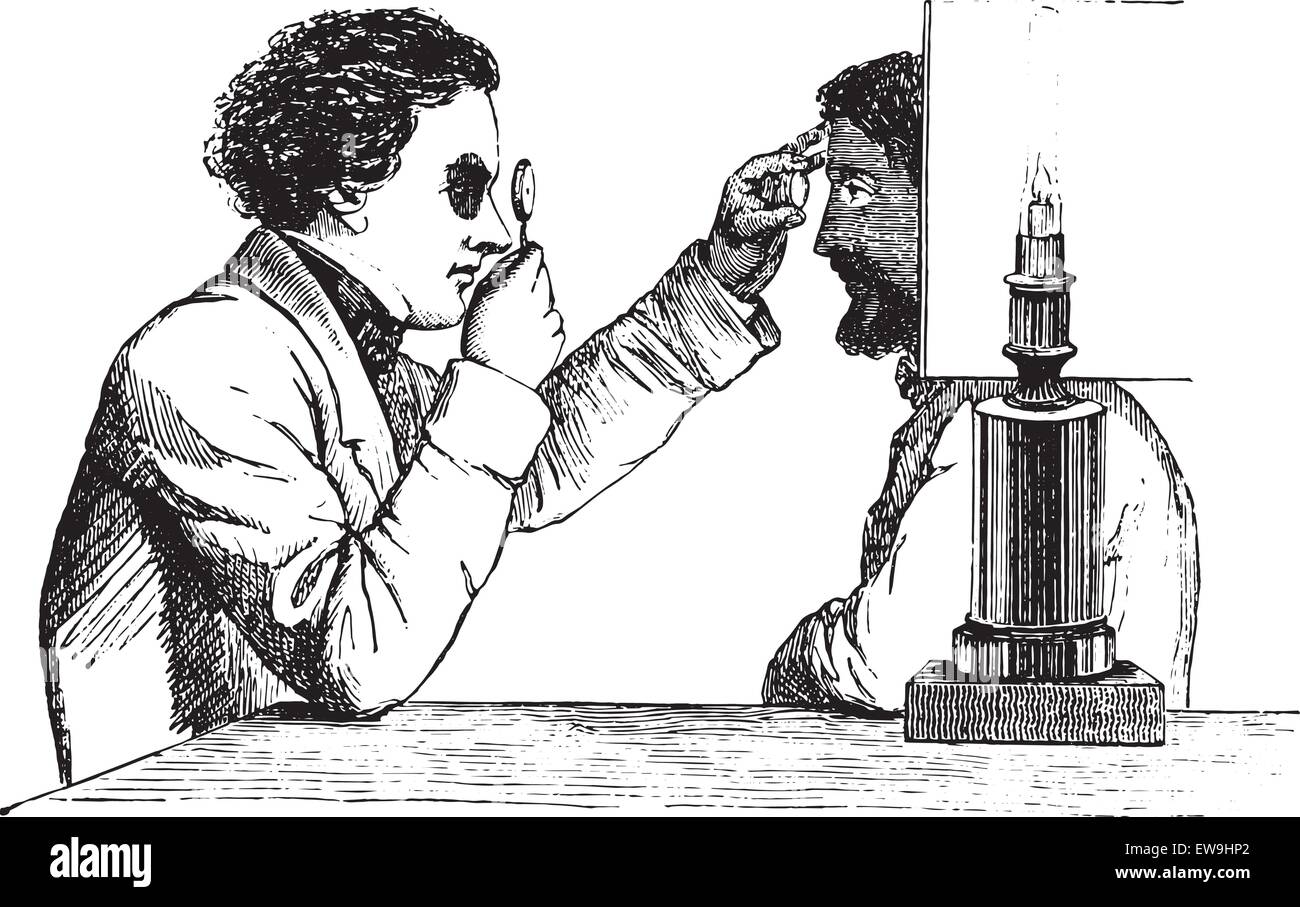

Ophthalmoscope, vintage engraved illustration. Usual Medicine Dictionary - Paul Labarthe - 1885. Stock Vectorhttps://www.alamy.com/image-license-details/?v=1https://www.alamy.com/stock-photo-ophthalmoscope-vintage-engraved-illustration-usual-medicine-dictionary-84419385.html

Ophthalmoscope, vintage engraved illustration. Usual Medicine Dictionary - Paul Labarthe - 1885. Stock Vectorhttps://www.alamy.com/image-license-details/?v=1https://www.alamy.com/stock-photo-ophthalmoscope-vintage-engraved-illustration-usual-medicine-dictionary-84419385.htmlRFEW9HP1–Ophthalmoscope, vintage engraved illustration. Usual Medicine Dictionary - Paul Labarthe - 1885.